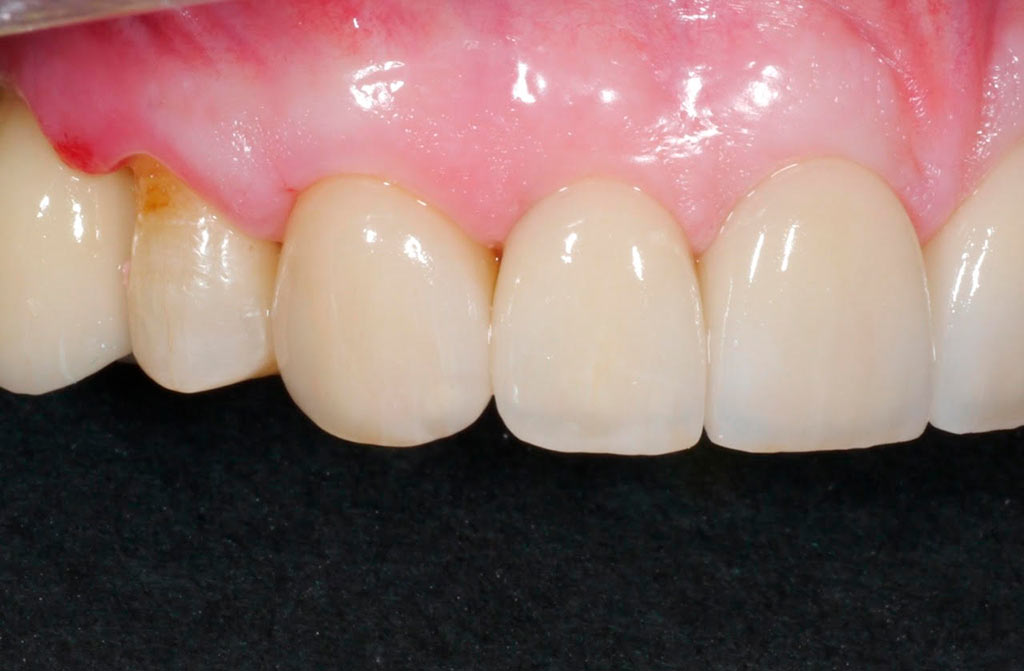

Completa inmediata,cirugía guiada, prótesis, puente de zirconio

Rehabilitacion de paciente con destrucción dental